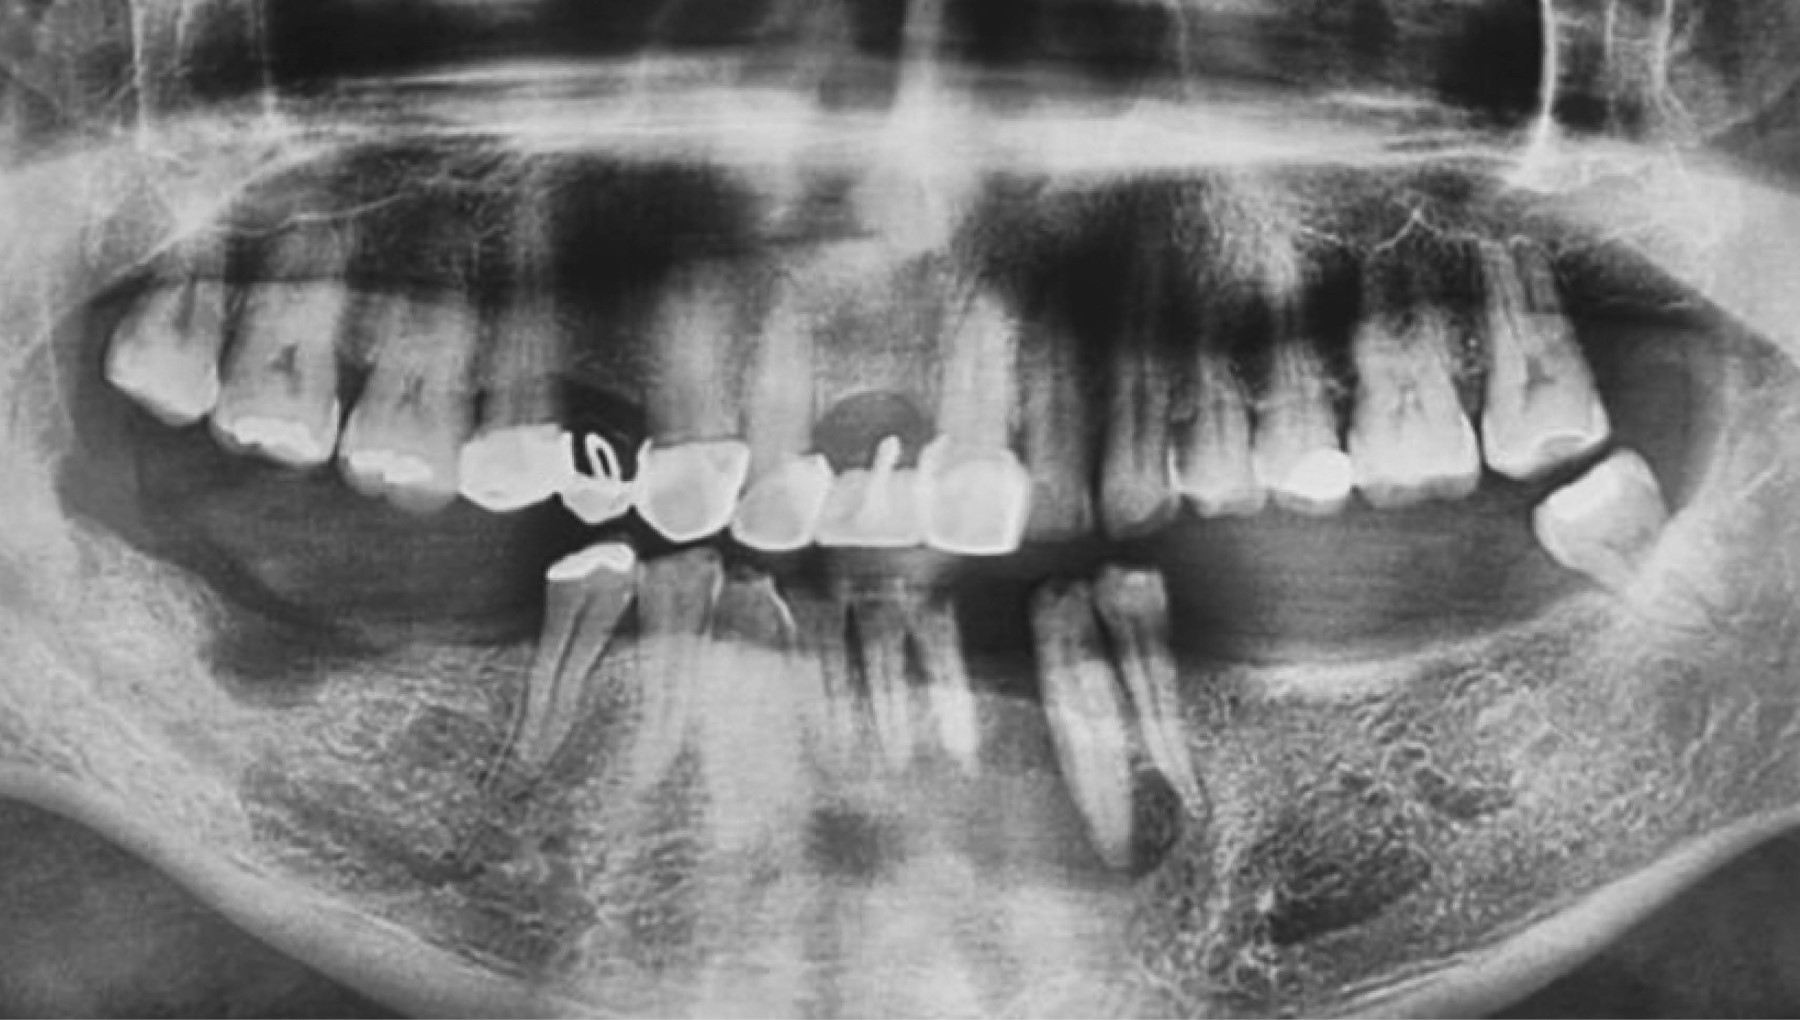

Presenta dolor 5/10 en escala visual analógica (EVA) en cuerpo mandibular izquierda, espontáneo, constante, sin exacerbación a la percusión horizontal y vertical de órgano dental canino izquierdo inferior. Niega presentar lesión en cuerpo, diaforesis o pérdida de peso repentina. Exploración extraoral sin evidencia de aumento de volumen, asimetrías o lesiones cutáneas-mucosas; intraoral, presenta defecto periodontal con recesión gingival asociado a órganos dentales incisivo central, lateral y canino inferiores izquierdos, con ulceración en región mencionada, movilidad grado III en órganos dentales mencionados (Figura 1). Sin presencia de adenomegalias cervicales a la palpación.

En la ortopantomografía con fecha 03/Agosto/2021, se observan lesiones osteolíticas; lesión radiolúcida multilocular con borde mal definidos en región posterior mandibular derecha, lesión radiolúcida unilocular bien definida asociada a órganos dentales incisivo lateral y canino izquierdo (dientes flotantes); y una lesión radiolúcida unilocular bien definida en borde alveolar de cuerpo mandibular derecho (Figura 2). En la ortopantomografía con fecha 24/Julio/2022 se observan dos de las tres lesiones osteolíticas mencionadas, siendo de menor tamaño de la región posterior mandibular derecha, de mayor tamaño la lesión asociada a órganos dentales incisivo lateral y canino izquierdo (dientes flotantes); y sin presencia de lesión en borde alveolar de cuerpo mandibular derecho.

Figura 1

Figura 2